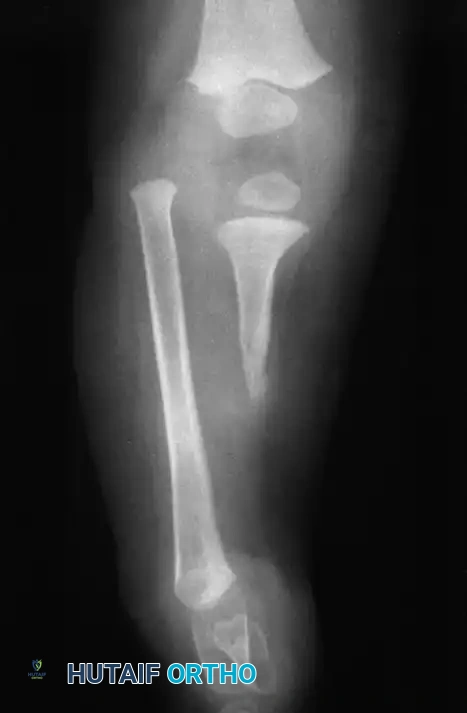

- Type 2 Deformity: A proximal tibia of varying size is present and ossified at birth. The fibula is usually normal in size, but the fibular head is proximally dislocated.

- Type 3 Deformity: The proximal tibia is not radiographically visible, but the distal tibial epiphysis is present. This is an exceptionally rare variant. The distal femoral epiphysis is usually well-formed, but the upper end of the fibula is proximally dislocated, leading to profound knee instability.

- Type 4 Deformity: The tibia is shortened, and there is proximal migration of the fibula with distal tibiofibular diastasis. This rare deformity is also referred to as congenital diastasis of the ankle joint. The distal tibial epiphysis may be entirely absent.

Clinically, the involved leg is significantly shortened. The fibular head is often palpable, particularly if it is proximally displaced into the popliteal fossa. The foot is typically held in severe, rigid equinovarus, and the hindfoot is profoundly stiff.

In older children, the proximal tibial anlage may be palpable upon deep clinical examination, even if it is not radiographically visible. The knee is generally flexed, and in more severe deformities, profound quadriceps insufficiency causes an absolute lack of active knee extension.

The treatment of choice is a proximal tibiofibular synostosis combined with a Syme amputation or complex distal reconstruction. Creating a synostosis between the fibula and the proximal tibia creates a uniform, in-line, weight-bearing mechanical axis. If the fibula is not surgically transferred and fused to the tibia, a peculiar, curved, hypertrophied fibula develops, causing a severe secondary deformity. Fusing the fibula underneath the tibia encourages its hypertrophy in a mechanically advantageous alignment.

For Type 1B and Type 2 tibial hemimelia, centralizing the mechanical axis is critical. The fibula must be brought under the mechanical axis of the femur or the existing proximal tibial anlage.

By fusing the fibula to the tibia, the surgeon prevents the progressive lateral bowing and hypertrophy of the fibula that inevitably occurs if it is left in its native, eccentric position. This synostosis provides a robust, centralized bony column that can later be lengthened or fitted with a prosthesis following a distal Syme amputation.